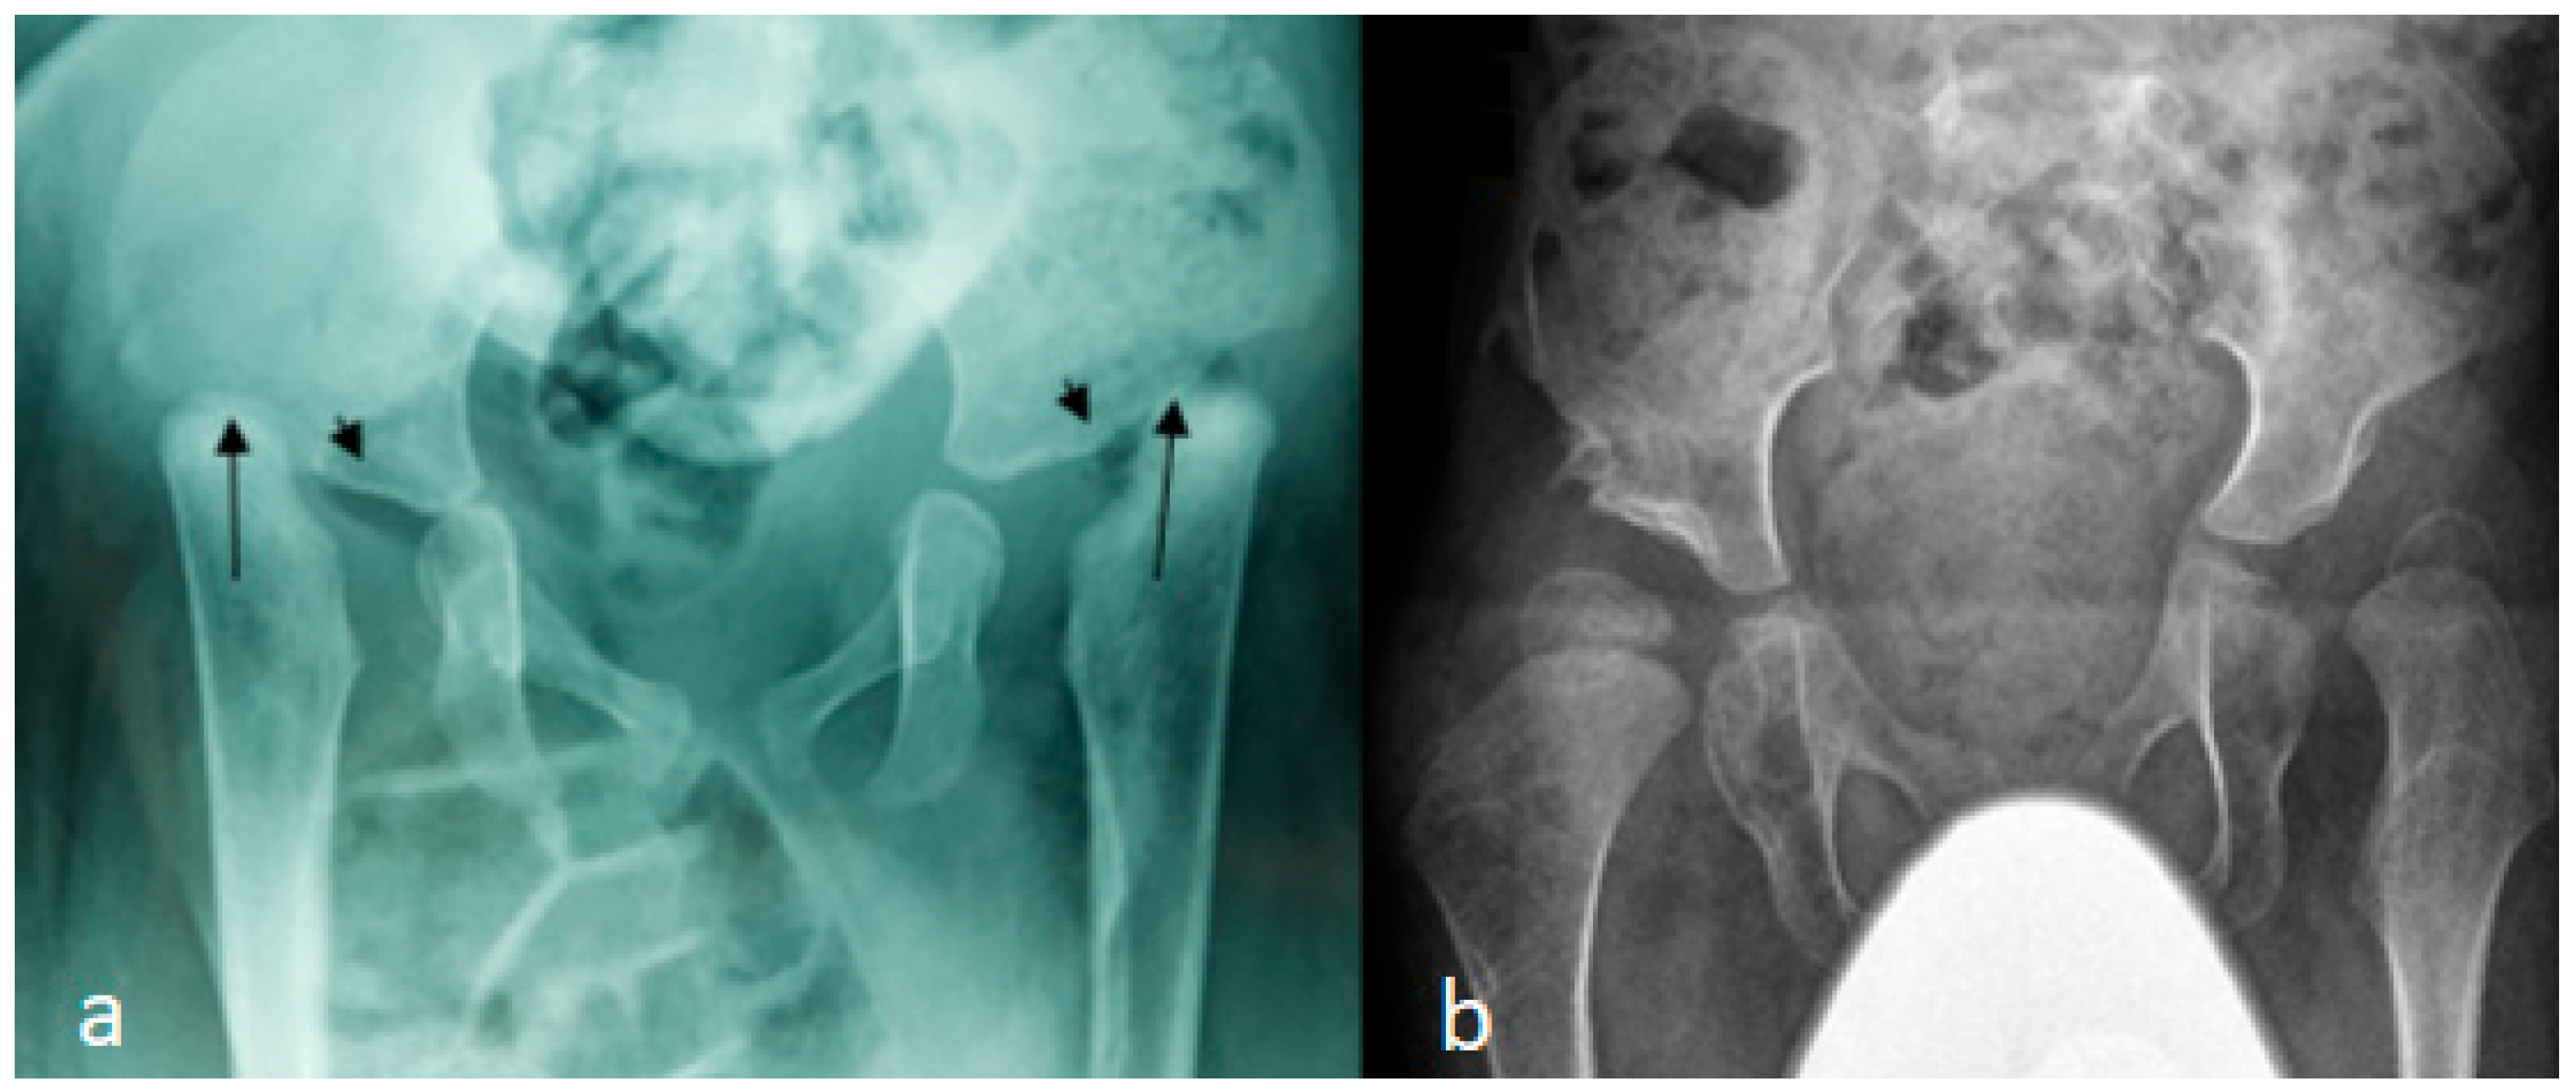

3.1. The Classical Clinical and Radiological Phenotype in Children with Larsen Syndrome

In these children, dysmorphic facial features were evident, which encompassed distinctive facial features, frontal bossing, and a flattened nasal bridge giving the facial phenotype of a dish-like facies. Our orthopedic strategy is based upon detailed clinical and radiological phenotypic characterization. Radiological phenotypic interpretations have been organized for all children by referring to 3D CT scan. In a lateral skull radiograph of a 7-month-old boy with Larsen syndrome, one can note brachycephaly, frontal bossing, and marked disproportionate small facial bones in comparison with a large cranium and dysplastic cervical spine, osteopenia of the lambdoid bones causing downward bulging, and prominence of the occipital bone associated with progressive thinning of the squamous part of the occipital bone (arrow). One can also note the cervical kyphosis (arrow) AP hand radiograph of a 3-year-old boy with Larsen syndrome showing retarded bone age, expansion of the distal ends of the shortened metacarpals, a thumb proximally placed, and the presence of accessory bone adjacent to the distal third metacarpal-phalangeal bone (arrow). One can also see the delta phalanx of the middle metacarpophalangeal bone of the fifth finger (arrow) (b) (Figure 1a,b). The AP pelvis radiograph of a 7-month-old girl with Larsen syndrome showed bilateral hip dislocation associated with maldevelopment of a severely dysplastic acetabulum and dysplastic capital femoral epiphysis (a). The AP pelvis radiograph of a 3-year-old boy with Larsen syndrome showed bilateral hip dislocations (severe acetabulo-femoral dysplasia) (Figure 2a). The AP pelvis radiograph of a 7-month-old girl with Larsen syndrome showed bilateral hip dislocation associated with maldevelopment of a severely dysplastic acetabulum and dysplastic capital femoral epiphysis (a). The AP pelvis radiograph of a 3-year-old boy with Larsen syndrome showed bilateral hip dislocations (severe acetabulo-femoral dysplasia) (Figure 2b). AP knees radiograph of a 5-month-old boy with Larsen syndrome showing bilateral knee dislocations (arrows) associated with under tubulation of the tibae and fibulae. Note the fragmented/deformed epiphyses and that the right tibia is medially subluxated. Note bilateral talipes equinivarus associated with double ossifications of the calcaneus (arrows) (Figure 3).

Figure 2.

(a,b): AP pelvis radiograph of a 7-month-old girl with Larsen syndrome showing bilateral hip dislocation associated with maldevelopment of severely dysplastic acetabulum and dysplastic capital femoral epiphysis (arrows) (a). AP pelvis radiograph of a 3-year-old boy with Larsen syndrome showing bilateral hip dislocations (severe acetabulo-femoral dysplasia) (b).